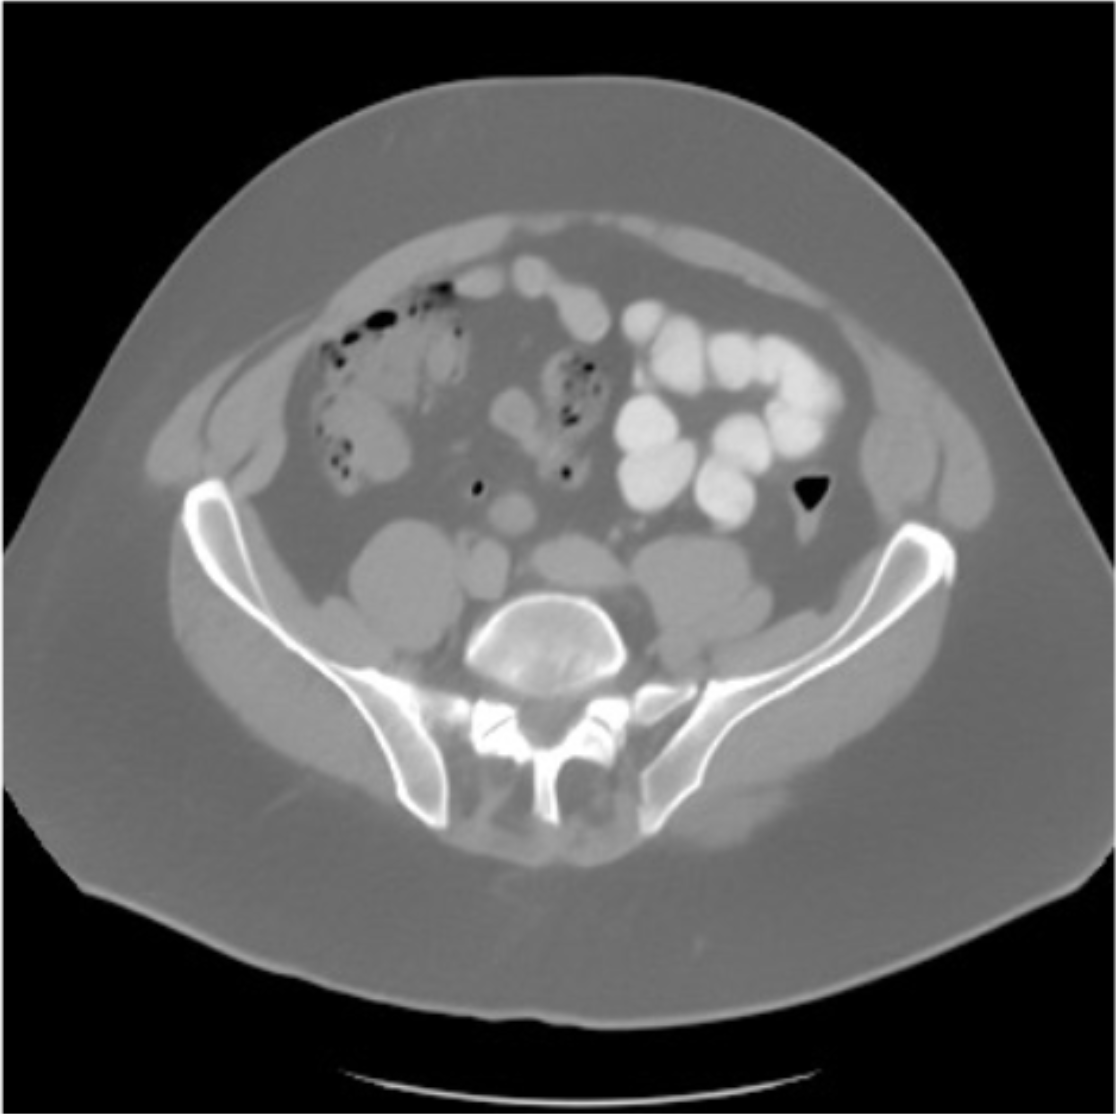

CT. Similar to MRI, limited-angle CT reconstruction has been a primary focus in CT research, aiming to reduce patient radiation exposure and enhance examination throughput. DM-based methods have shown remarkable performance in this reconstruction task. For example, Liu et al. [12] introduce DOLCE, a method specifically designed for limited-angle CT reconstruction within a DDPM framework. Conventionally, the Filtered Back Projection (FBP) algorithm [118] is employed to map CT images from sinograms, leveraging the Fourier slice theorem. However, limited-angle measurements lead to Fourier measurement loss and subsequently degraded reconstruction outcomes.

Due to the ill-posed nature, directly using DDPM presents challenges. Following the design in inpainting tasks, DOLCE [12] integrates the FBP output on limited sinograms as prior information to condition the diffusion model (Fig. 15). Additionally, DOLCE enforces a consistency term in the denoising iteration to ensure reconstruction consistency through iterative refinement using proximal mapping in the inference step to meet the consistency conditions presented by sinograms. Evaluation on C4KC-KiTS verifies DOLCE’s effectiveness in generating high-quality CT images. Moreover, the reconstruction performance is further evaluated in downstream tasks such as 3D Segmentation.